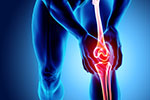

Eine Arthrose ist mit einer zunehmenden Schädigung des Knorpels oder einem Verlust der Knorpelmasse in einem oder mehreren Gelenken verbunden.

Darum ist die Arthrose auch unter dem Begriff „Gelenkverschleiß“ bekannt.

In einem gesunden Gelenk wirkt der Knorpel wie ein Gummipuffer und übernimmt die Stoßdämpferfunktion bei Bewegungen. Die im Gelenkspalt befindliche Gelenkflüssigkeit versorgt den Knorpel mit Nährstoffen. Bei zu wenig Bewegung, extremer Beanspruchung oder durch das fortschreitende Alter trocknet der Knorpel im Laufe der Jahre aus, rubbelt sich wie ein Radiergummi ab und führt zu einer Gelenkentzündung. Die dabei freigesetzten Stoffe zersetzen den Knorpel noch weiter, die Beweglichkeit des Gelenkes nimmt immer weiter ab.

Doch je weniger ein Gelenk bewegt wird, desto schlechter wird der Knorpel durch die Gelenkflüssigkeit ernährt und desto schneller schreitet die so genannte Arthrose fort.

Folgen dieses Gelenkverschleißes sind Schmerzen und Steifigkeit des betroffenen Gelenks und zunehmende Verformung. Im Endstadium der Arthrose kann das Gelenk vollständig verknöchern. Der Prozess kann durch verschiedene Maßnahmen verzögert werden, in schweren Fällen von Arthrose ist jedoch ein operativer Gelenkersatz nötig.